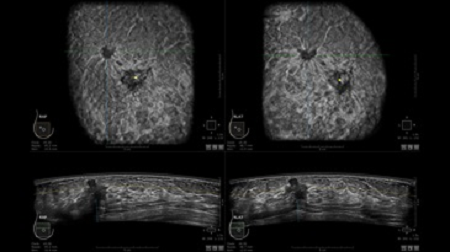

• Получение объемных 3D изображений с возможностью покадрового просмотра

• Получение изображений в поперечной плоскости (в реальном времени) и в коронарной плоскости (статическая, для указания нахождения соска)

• Отображение объемных 3D ультразвуковых изображений, которые состоят из традиционных поперечных и воссозданных коронарных и сагиттальных проекций

• Возможность отображения полного 3D изображения

• Стандартизованная ориентация изображения: «толстый срез» в коронарной плоскости; поперечная; сагиттальная плоскость; радиальный и антирадиальный поворот изображения; просмотр исключительно области интереса

• Одновременный просмотр двух изображений для сопоставления в коронарной плоскости